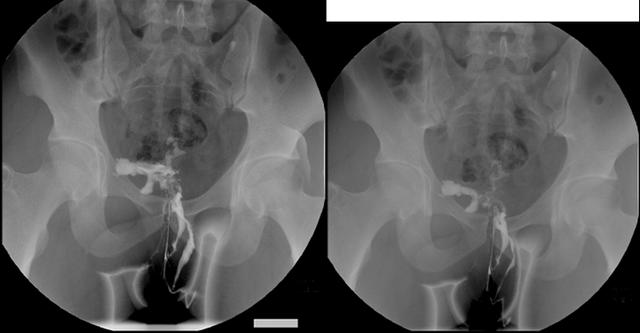

探针经外口可插入管道;经外口注入亚甲蓝,肛管内纱布蓝染,瘘口造影,可显示管道影像。

骨盆化脓性或结核性病变引起的骨盆骨髓炎,常在会阴部发生窦道,与肛瘘的外口极为相似。但前者无内口,X 线片显示骨盆有病变。

4、骶尾部骨结核:

发病缓慢,无红肿热痛等急性炎症变化,破溃后流出稀薄脓液,外口较大,边缘不整齐,且经久不愈。X 线片显示骶尾骨有骨质损害和结核病灶。

5、骶尾部畸胎瘤:

破溃后可形成尾骨前瘘或直肠内瘘。大型畸胎瘤可突出骶尾部,容易诊断;小型无症状的肿瘤,可在直肠后方扪及平滑、有分叶的肿块。X 线片可见骶骨和直肠之间有肿块,内有不定形的散在钙化阴影,可见骨质或牙。